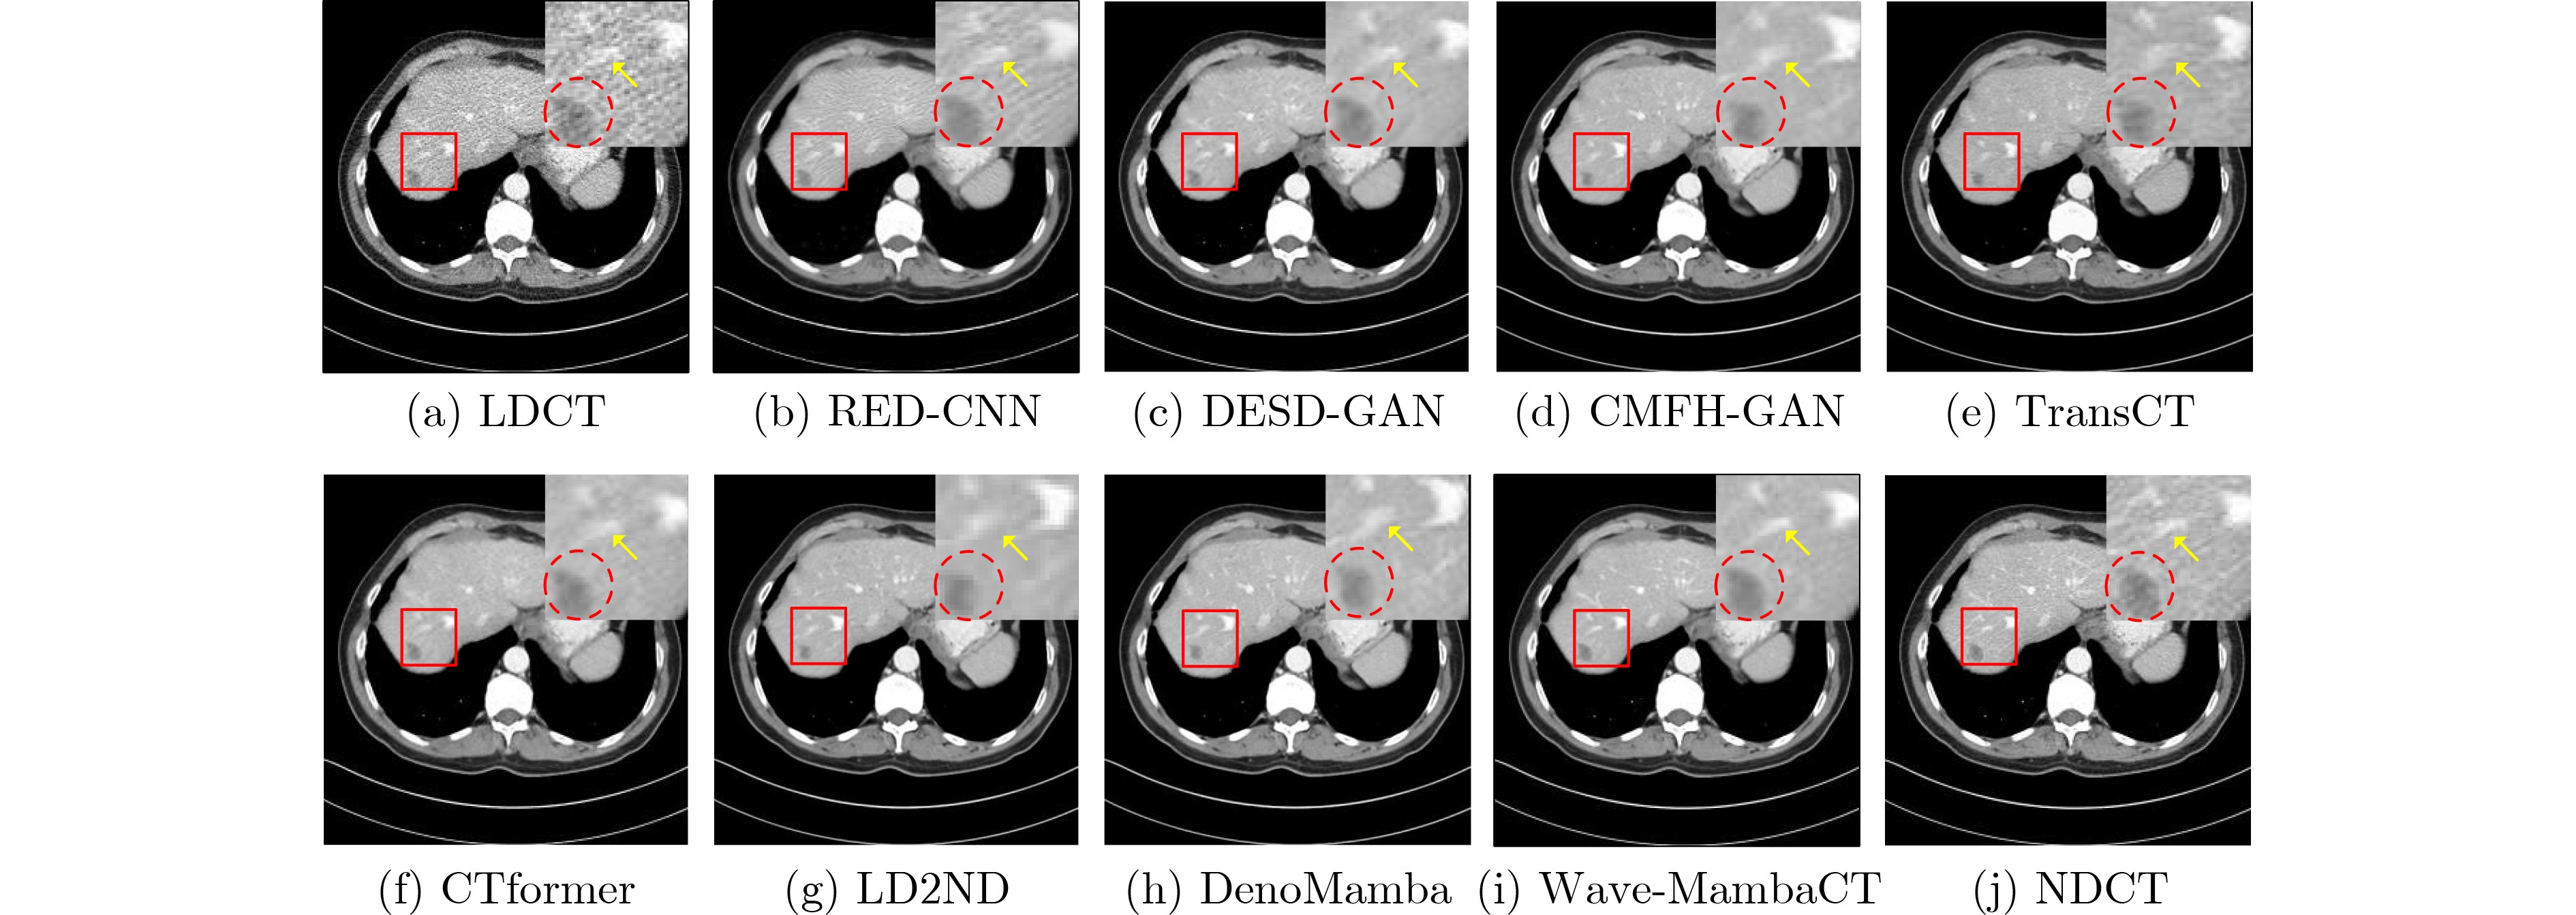

•   Objective  Low-Dose Computed Tomography (LDCT) reduces patient radiation exposure but introduces substantial noise and artifacts into reconstructed images. Convolutional Neural Network (CNN)-based denoising approaches are limited by local receptive fields, which restrict their abilities to capture long-range dependencies. Transformer-based methods alleviate this limitation but incur quadratic computational complexity relative to image size. In contrast, State Space Model (SSM)–based Mamba frameworks achieve linear complexity for long-range interactions. However, existing Mamba-based methods often suffer from information loss and insufficient noise suppression. To address these limitations, we propose the Wave-MambaCT model.  Methods  The proposed Wave-MambaCT model adopts a multi-scale framework that integrates Discrete Wavelet Transform (DWT) with a Mamba module based on the SSM. First, DWT performs a two-level decomposition of the LDCT image, decoupling noise from Low-Frequency (LF) content. This design directs denoising primarily toward the High-Frequency (HF) components, facilitating noise suppression while preserving structural information. Second, a residual module combined with a Spatial-Channel Mamba (SCM) module extracts both local and global features from LF and HF bands at different scales. The noise-free LF features are then used to correct and enhance the corresponding HF features through an attention-based Cross-Frequency Mamba (CFM) module. Finally, inverse wavelet transform is applied in stages to progressively reconstruct the image. To further improve denoising performance and network stability, multiple loss functions are employed, including L1 loss, wavelet-domain LF loss, and adversarial loss for HF components.  Results and Discussions  Extensive experiments on the simulated Mayo Clinic datasets, the real Piglet datasets, and the hospital clinical dataset DeepLesion show that Wave-MambaCT provides superior denoising performance and generalization. On the Mayo dataset, a PSNR of 31.6528 is achieved, which is higher than that of the suboptimal method DenoMamba (PSNR 31.4219), while MSE is reduced to 0.00074 and SSIM and VIF are improved to 0.8851 and 0.4629, respectively (Table 1). Visual results (Figs. 46) demonstrate that edges and fine details such as abdominal textures and lesion contours are preserved, with minimal blurring or residual artifacts compared with competing methods. Computational efficiency analysis (Table 2) indicates that Wave-MambaCT maintains low FLOPs (17.2135 G) and parameters (5.3913 M). FLOPs are lower than those of all networks except RED-CNN, and the parameter count is higher only than those of RED-CNN and CTformer. During training, 4.12 minutes per epoch are required, longer only than RED-CNN. During testing, 0.1463 seconds are required per image, which is at a medium level among the compared methods. Generalization tests on the Piglet datasets (Figs. 7, 8, Tables 3, 4) and DeepLesion (Fig. 9) further confirm the robustness and generalization capacity of Wave-MambaCT.In the proposed design, HF sub-bands are grouped, and noise-free LF information is used to correct and guide their recovery. This strategy is based on two considerations. First, it reduces network complexity and parameter count. Second, although the sub-bands correspond to HF information in different orientations, they are correlated and complementary as components of the same image. Joint processing enhances the representation of HF content, whereas processing them separately would require a multi-branch architecture, inevitably increasing complexity and parameters. Future work will explore approaches to reduce complexity and parameters when processing HF sub-bands individually, while strengthening their correlations to improve recovery. For structural simplicity, SCM is applied to both HF and LF feature extraction. However, redundancy exists when extracting LF features, and future studies will explore the use of different Mamba modules for HF and LF features to further optimize computational efficiency.  Conclusions  Wave-MambaCT integrates DWT for multi-scale decomposition, a residual module for local feature extraction, and an SCM module for efficient global dependency modeling to address the denoising challenges of LDCT images. By decoupling noise from LF content through DWT, the model enables targeted noise removal in the HF domain, facilitating effective noise suppression. The designed RSCM, composed of residual blocks and SCM modules, captures fine-grained textures and long-range interactions, enhancing the extraction of both local and global information. In parallel, the Cross-band Enhancement Module (CEM) employs noise-free LF features to refine HF components through attention-based CFM, ensuring structural consistency across scales. Ablation studies (Table 5) confirm the essential contributions of both SCM and CEM modules to maintaining high performance. Importantly, the model’s staged denoising strategy achieves a favorable balance between noise reduction and structural preservation, yielding robustness to varying radiation doses and complex noise distributions.